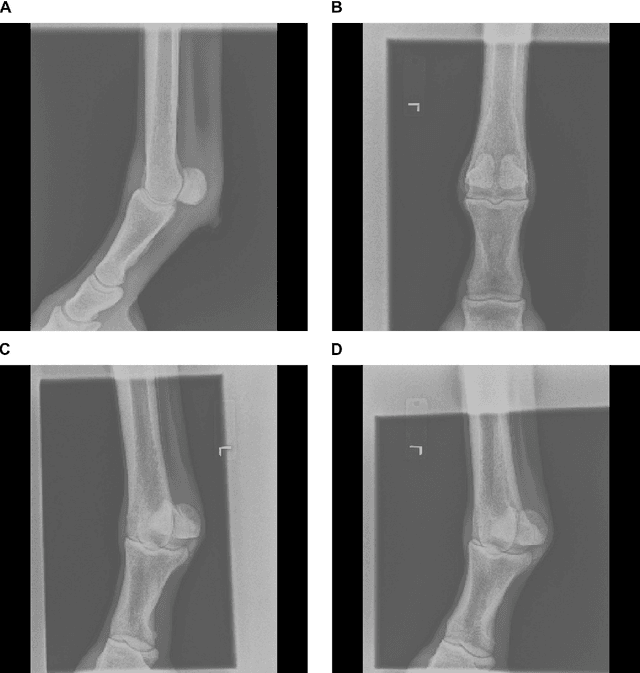

Abstract:Background: Object detection in radiograph computer vision has largely benefited from progress in deep convolutional neural networks and can, for example, annotate a radiograph with a box around a knee joint or intervertebral disc. Is deep learning capable of detect small (less than 1% of the image) in radiographs? And how many radiographs do we need use when re-training a deep learning model? Methods: We annotated 396 radiographs of left and right carpi dorsal 75 medial to palmarolateral oblique (DMPLO) projection with the location of radius, proximal row of carpal bones, distal row of carpal bones, accessory carpal bone, first carpal bone (if present), and metacarpus (metacarpal II, III, and IV). The radiographs and respective annotations were splited into sets that were used to leave-one-out cross-validation of models created using transfer learn from YOLOv5s. Results: Models trained using 96 radiographs or more achieved precision, recall and mAP above 0.95, including for the first carpal bone, when trained for 32 epochs. The best model needed the double of epochs to learn to detect the first carpal bone compared with the other bones. Conclusions: Free and open source state of the art object detection models based on deep learning can be re-trained for radiograph computer vision applications with 100 radiographs and achieved precision, recall and mAP above 0.95.